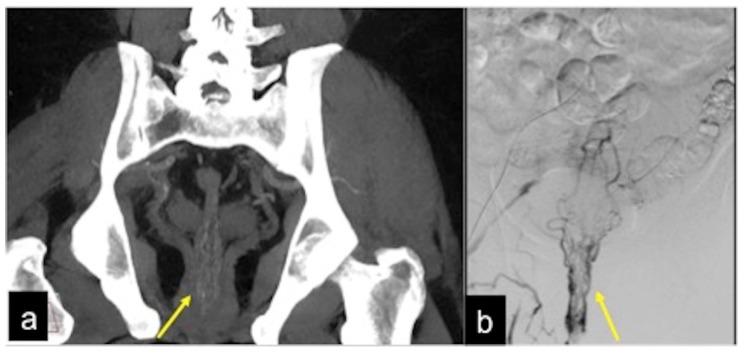

CT 血管造影在急性胃肠道出血中的作用:活跃和隐匿性发现的影像学描述。

The Role of CT-Angiography in the Acute Gastrointestinal Bleeding: A Pictorial Essay of Active and Obscure Findings.

Gastrointestinal bleeding is a potentially life-threatening abdominal emergency that remains a common cause of hospitalisation. Although 80-85% of cases of gastrointestinal bleeding resolve spontaneously, it can result in massive haemorrhage and death. The presentation of gastrointestinal bleeding can range from asymptomatic or mildly ill patients requiring only conservative treatments to severely ill patients requiring immediate intervention. Identifying the source of the bleeding can be difficult due to the wide range of potential causes, the length of the gastrointestinal tract and the intermittent nature of the bleeding. The diagnostic and therapeutic approach is fully dependent on the nature of the bleeding and the patient's haemodynamic status. Radiologists should be aware of the appropriate uses of computed tomography angiography and other imaging modalities in patients with acute gastrointestinal bleeding, as well as the semiotics of bleeding and diagnostic pitfalls in order to appropriately diagnose and manage these patients. The learning objective of this review is to illustrate the computed tomography angiography technique, including the potential role of dual-energy computed tomography angiography, also highlighting the tips and tricks to identify the most common and uncommon features of acute gastrointestinal bleeding and its obscure form.

胃肠道出血是一种潜在的危及生命的腹部急症,仍然是导致住院的常见原因。尽管 80-85%的胃肠道出血病例会自发缓解,但它可能导致大量出血和死亡。胃肠道出血的表现范围从无症状或轻度不适的患者仅需保守治疗到需要立即干预的严重疾病患者。由于潜在原因广泛、胃肠道长度长以及出血间歇性,确定出血部位可能很困难。诊断和治疗方法完全取决于出血的性质和患者的血流动力学状态。放射科医生应该了解在急性胃肠道出血患者中使用计算机断层血管造影和其他成像方式的适当用途,以及出血的征象和诊断陷阱,以便对这些患者进行适当的诊断和治疗。本次综述的学习目标是说明计算机断层血管造影技术,包括双能计算机断层血管造影的潜在作用,还强调了识别急性胃肠道出血及其隐匿形式的最常见和不常见特征的技巧和窍门。